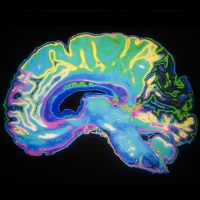

New dye gives scientists a clearer insight into the brain

Posted on 16 November 2017 Keele University researchers have designed a new dye that can be used to observe the electrical activity of neurons in the brain and could lead to finding a new and more efficient way of treating neurological diseases, as presented at the prestigious Society for Neuroscience annual conference in Washington, D.C. this week.